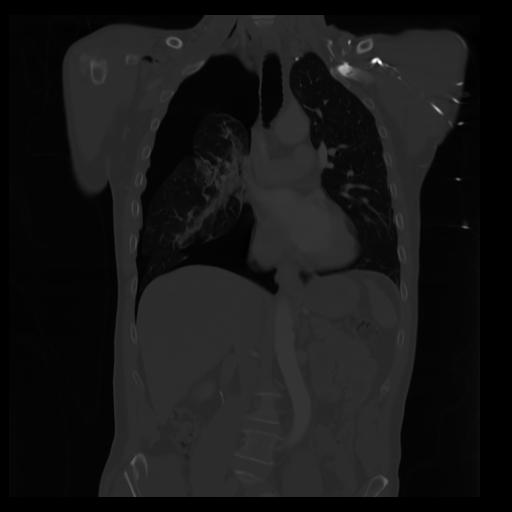

29 CUERPO,CE,Coronal,3.000,CUERPO,Coronal,